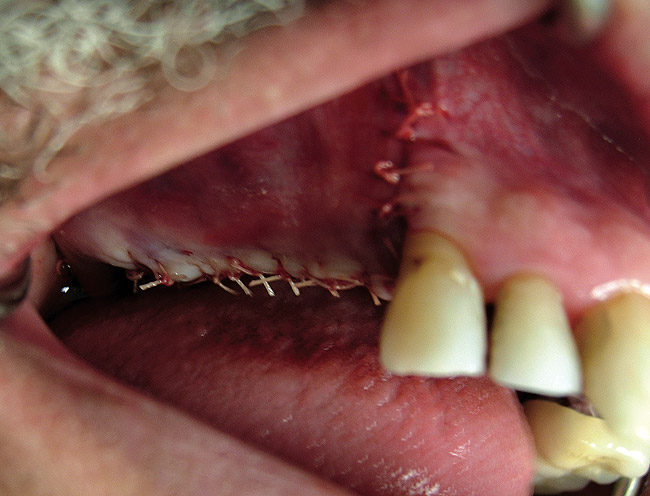

Drugs that are often prescribed are amoxicillin 500 mg tid or clindamycin 300 mg tid for 10 days, glucocorticoids (dexamethasone 4 mg for 2 days), ibuprofen 600 mg every 4 to 6 hours for pain if needed, and 0.12% chlorhexidine twice daily for 10 days (Figure 7).

Figure  7  The graft after suturing.

Figure 7